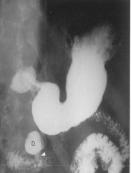

Une diverticule de bord

interieure de D3 |

Imageradiologique du diverticule D4 et a

jejunum proximale . |